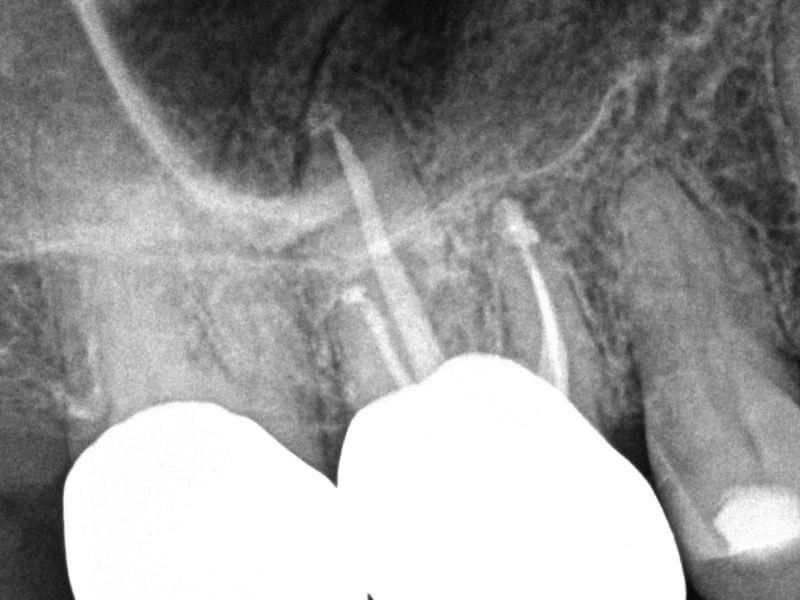

74-year-old female presented with biting tenderness for five days. History of RCT 50 years ago. Clinical testing revealed Tooth #3 was tender to percussion, biting and grinding. Diagnosis: #3 previously treated and symptomatic apical periodontitis. Treatment plan: silver point retreatment #3. Accessed, removed silver points, shaped canals with ProTaper Gold®GentleWave® Procedure with ProControl™ completed. Obturated with TruNatomy® 25 GP and BC Sealer HiFlow™. BC Liner™ over orifices.

Pre